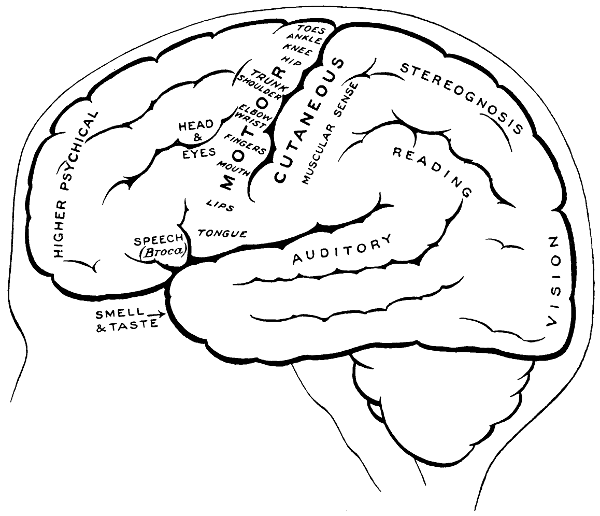

| 3. The cortical motor and sensory areas | 8 |

| 58. The cortical motor and sensory areas | 165 |

| 68. The cortical motor and sensory areas | 220 |

The researches of Sherrington and Grünbaum,[2] Campbell,[3] and others tend to show that the cortical motor areas are situated entirely anterior to the central fissure or fissure of Rolando, extending above well over on to the mesial aspect of the brain, though not so far as the calloso-marginal fissure, and in the downward direction to within a short distance of the fissure of Sylvius. In the posterior direction the motor area includes the anterior boundary and part of the bottom of the fissure of Rolando, whilst in front it spreads, by means of gyri annectantes, on to that part of the brain which lies anterior to the precentral sulcus. The anterior termination is indefinite, but the motor strip is, on an average, not more than 3⁄4 inch in breadth.

The genua of the Rolandic fissure are said to bear a more or less definite relation to the motor areas. In my experience, however, they are too variable, and any importance which might obtain is further diminished by the fact that the surgeon should never rest content with that limited exposure of the brain which was so much in vogue till recent years. The suspected region is widely exposed by osteoplastic flap, and if doubt exists as to the particular part of cortex exposed the question is accurately settled by faradization.

[8]

This motor strip corresponds, from above downwards, to the movements of the contralateral lower extremity (toe to hip), trunk, upper extremity (shoulder to fingers), neck and face. It is a point of some general utility to bear in mind that the temporal crest intervenes approximately between the regions responsible for the movements of the upper extremity (above the crest) and those for the movements of the head and face (below the crest).

Fig. 3. The Cortical Motor and Sensory Areas.

On the left side of the head—in normal right-handed individuals—the motor speech area of Broca corresponds to the third left frontal convolution, in the angle between the anterior and posterior horizontal limbs of the Sylvian fissure.

The ‘primary registration’ of ‘common sensation’ occurs in the post-central gyrus, immediately posterior to the fissure of Rolando. This tactile area occupies a position behind the fissure of Rolando[9] similar in extent to that occupied by the motor area in front. It commences at the bottom of the fissure of Rolando and extends backwards over rather more than half the exposed area of the post-central convolution. It reaches down to near the Sylvian fissure and extends over on to the mesial aspect of the brain. Furthermore, it is probable that sensation in any given part lies on more or less the same level as the corresponding motor area.

Immediately posterior to the tactile area and occupying the posterior and upper part of the post-central convolution, the area responsible for muscle-sense is situated.

Stereognosis—memory pictures, object perception, &c.—is referred to the superior parietal lobe.

Primary visual impressions are received in the occipital lobe, more especially on the mesial aspect thereof.

Finally, the four areas concerned in speech—motor speech, writing, reading, and hearing—are anatomically separated from one another and yet closely associated, so much so that one can hardly be involved without the other. The motor speech centre of Broca has already been mentioned as occupying—in right-handed individuals—the posterior part of the third left frontal convolution. Writing lies immediately above and in front, in the posterior part of the middle frontal gyrus, auditory impressions are received in the posterior and upper part of the first temporo-sphenoidal lobe, whilst the power of reading is dependent on the integrity of the supramarginal and angular gyri (see also Fig. 57).

Smell and Taste lie in close relation to the anterior pole of the temporo-sphenoidal lobes.